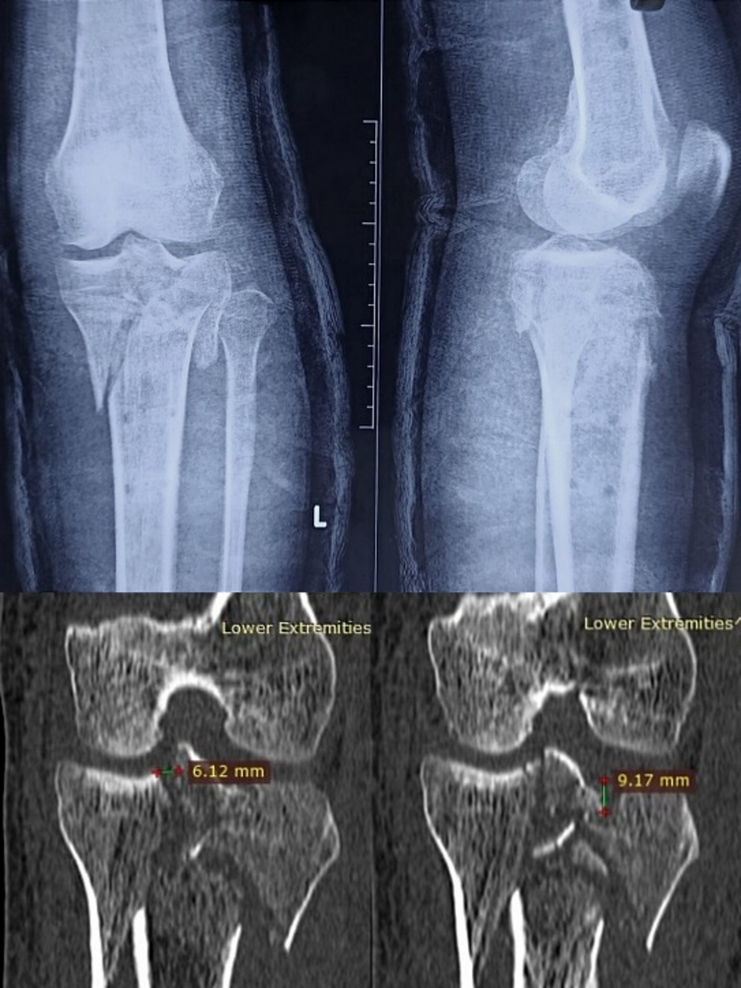

X-ray and CT scan images before the surgery.